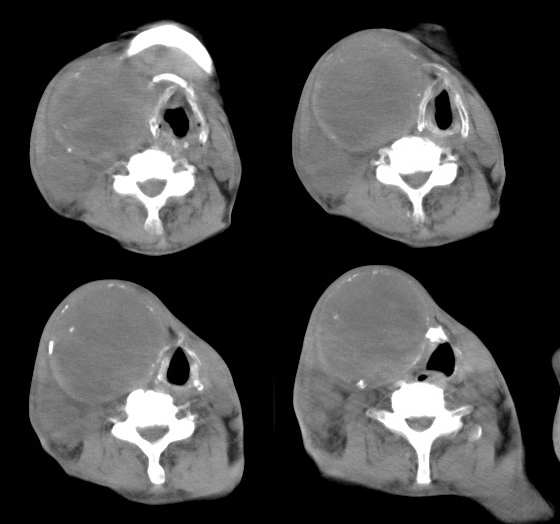

男,74岁,甲状腺肿30余年。现右颈部出现新肿块,疼痛,感乏力。

右颈部巨大软组织肿块影,范围较广,上至下颌角,下至颈静脉切迹。其最大层面位于右侧甲状腺区。肿块密度不均,其中有坏死液化区和班片状钙影,增强扫描见肿块实质区有强化。邻近结构挤压移位,部分结构侵蚀破坏,右侧多个颈深淋巴结肿大。两肺弥漫分布小结节影,以胸膜下为主,其大小不等,边缘光整。右侧胸壁亦见软组织结节影,纵隔多个淋巴结肿大及两侧锁骨上淋巴结肿大。

意见:右侧甲状腺癌并两肺、胸壁、纵隔淋巴结、颈深淋巴结、锁骨上淋巴结等广泛转移。